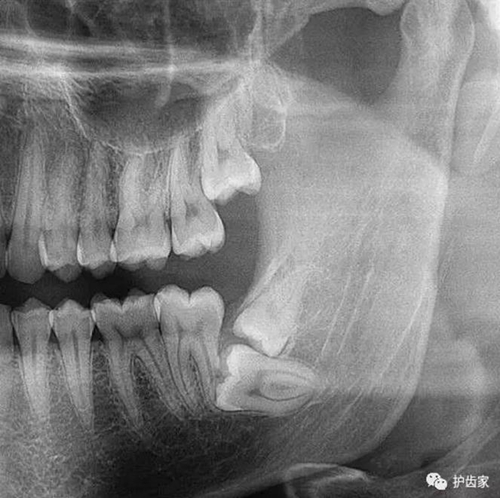

根神經(jīng)線位置千變?nèi)f化,有些離智齒牙根很遠(yuǎn),有些很近,有些甚至穿過智齒根部。

拍片是為了了解智齒周圍情況,也是為了了解智齒結(jié)構(gòu),牙根結(jié)構(gòu)千變?nèi)f化,有可能是融合成一個根,也可能是八爪根。不同牙根不同位置及方向,只有通過拍片來確認(rèn)。

拍片也為了了解下頜神經(jīng)與智齒的關(guān)系,一般離得近,有醫(yī)療風(fēng)險的,基本沒有醫(yī)生愿意拔,現(xiàn)在沒人為了幾百元,賠上自己的職業(yè)生涯。誰都怕拔智齒,敲打智齒,一不小心,碰到神經(jīng),就攤上大事了。有理都說不清。

通過拍片可以了解牙齒本身:生長方向,牙根數(shù)目,牙根是否彎曲,膨大等。

與重要解剖結(jié)構(gòu)的位置關(guān)系:如上頜磨牙與上頜竇的關(guān)系;下頜磨牙與下頜神經(jīng)管的關(guān)系;兒童在混合牙列期恒牙與乳牙胚的關(guān)系等??梢詼p少拔牙的風(fēng)險。